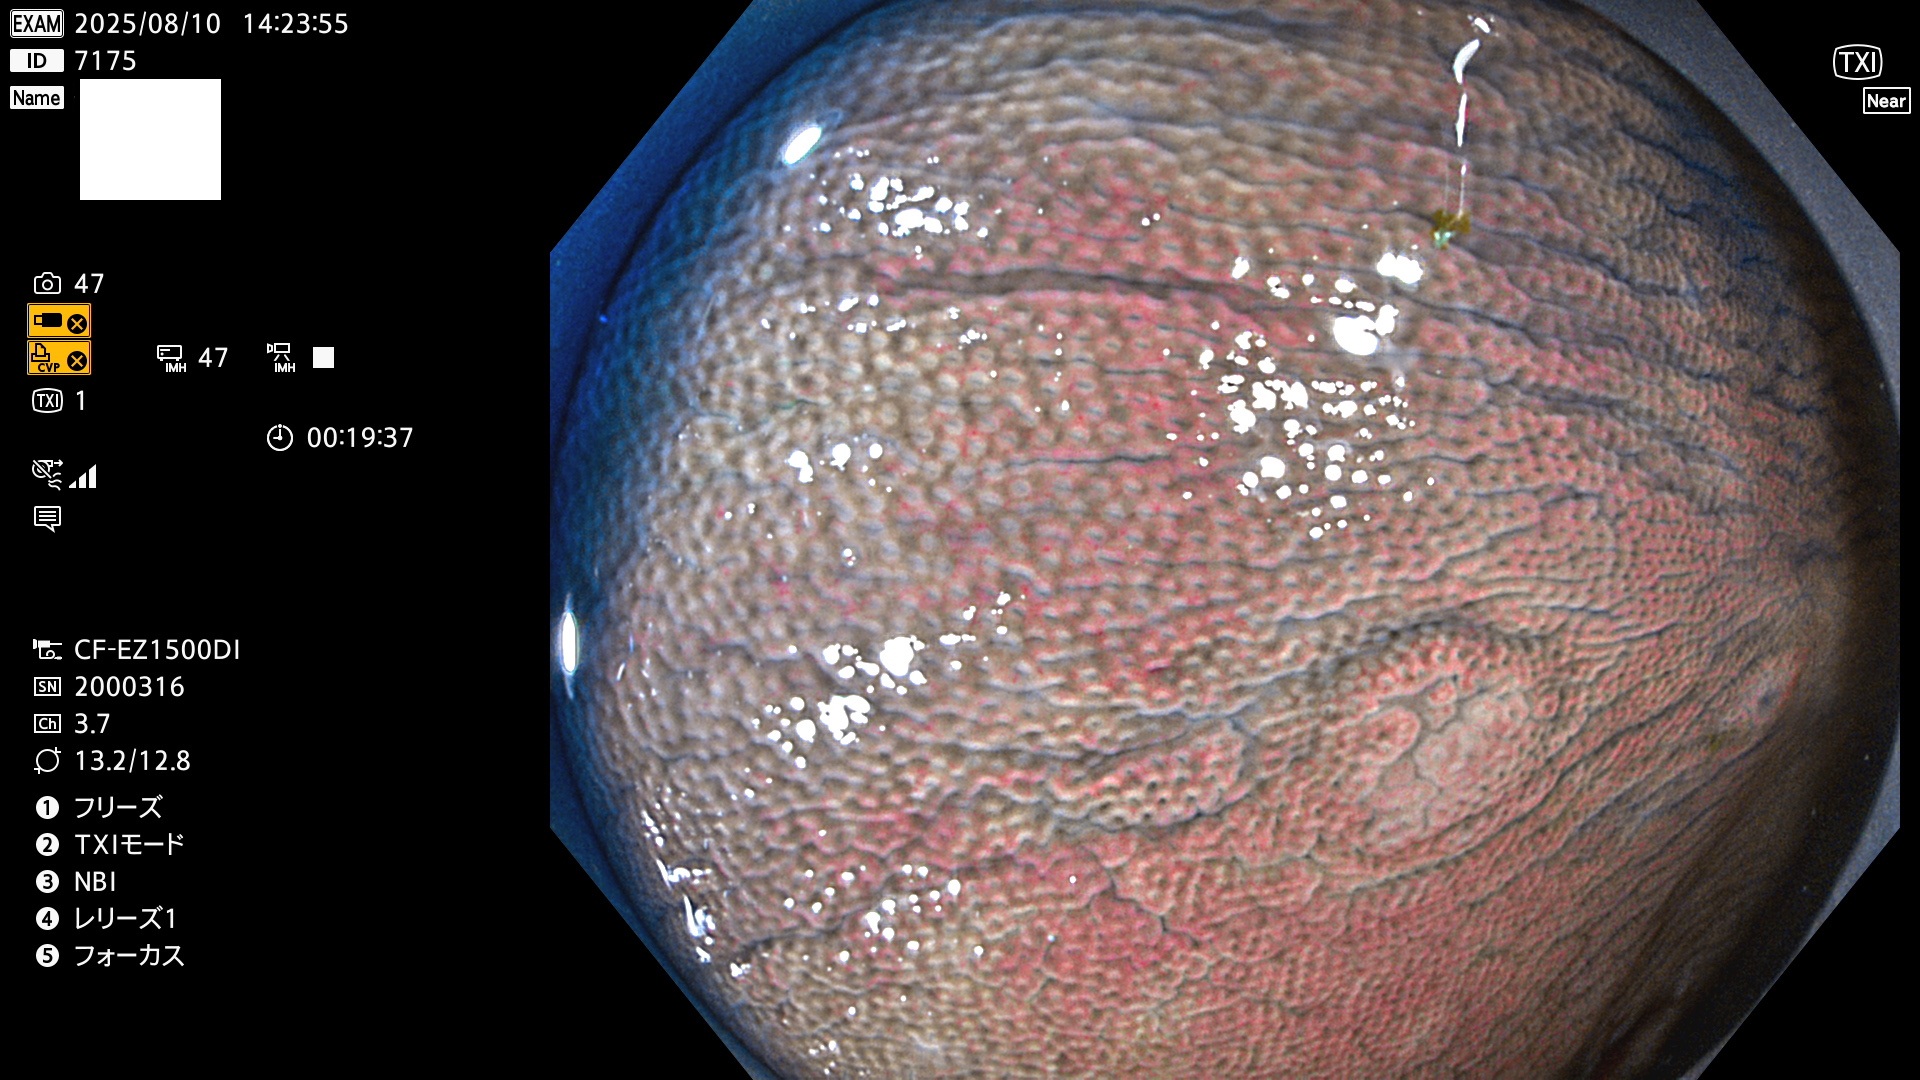

完全に平坦な物をUb、陥凹している物をUcと呼びます。Ubは認識が困難で、Ucはびらん(炎症)と紛らわしいために見落とされやすく、「内視鏡後・大腸癌」の原因になります。

毎週の検査(木・金・土・日)に発見されたUbとUc型・腺腫を、その週の日曜の夜にUPし1週間、提示します。

2025年8月7日〜8月10日の4日間(35件)6個 (Uc_ADR=6個/35人=17%)